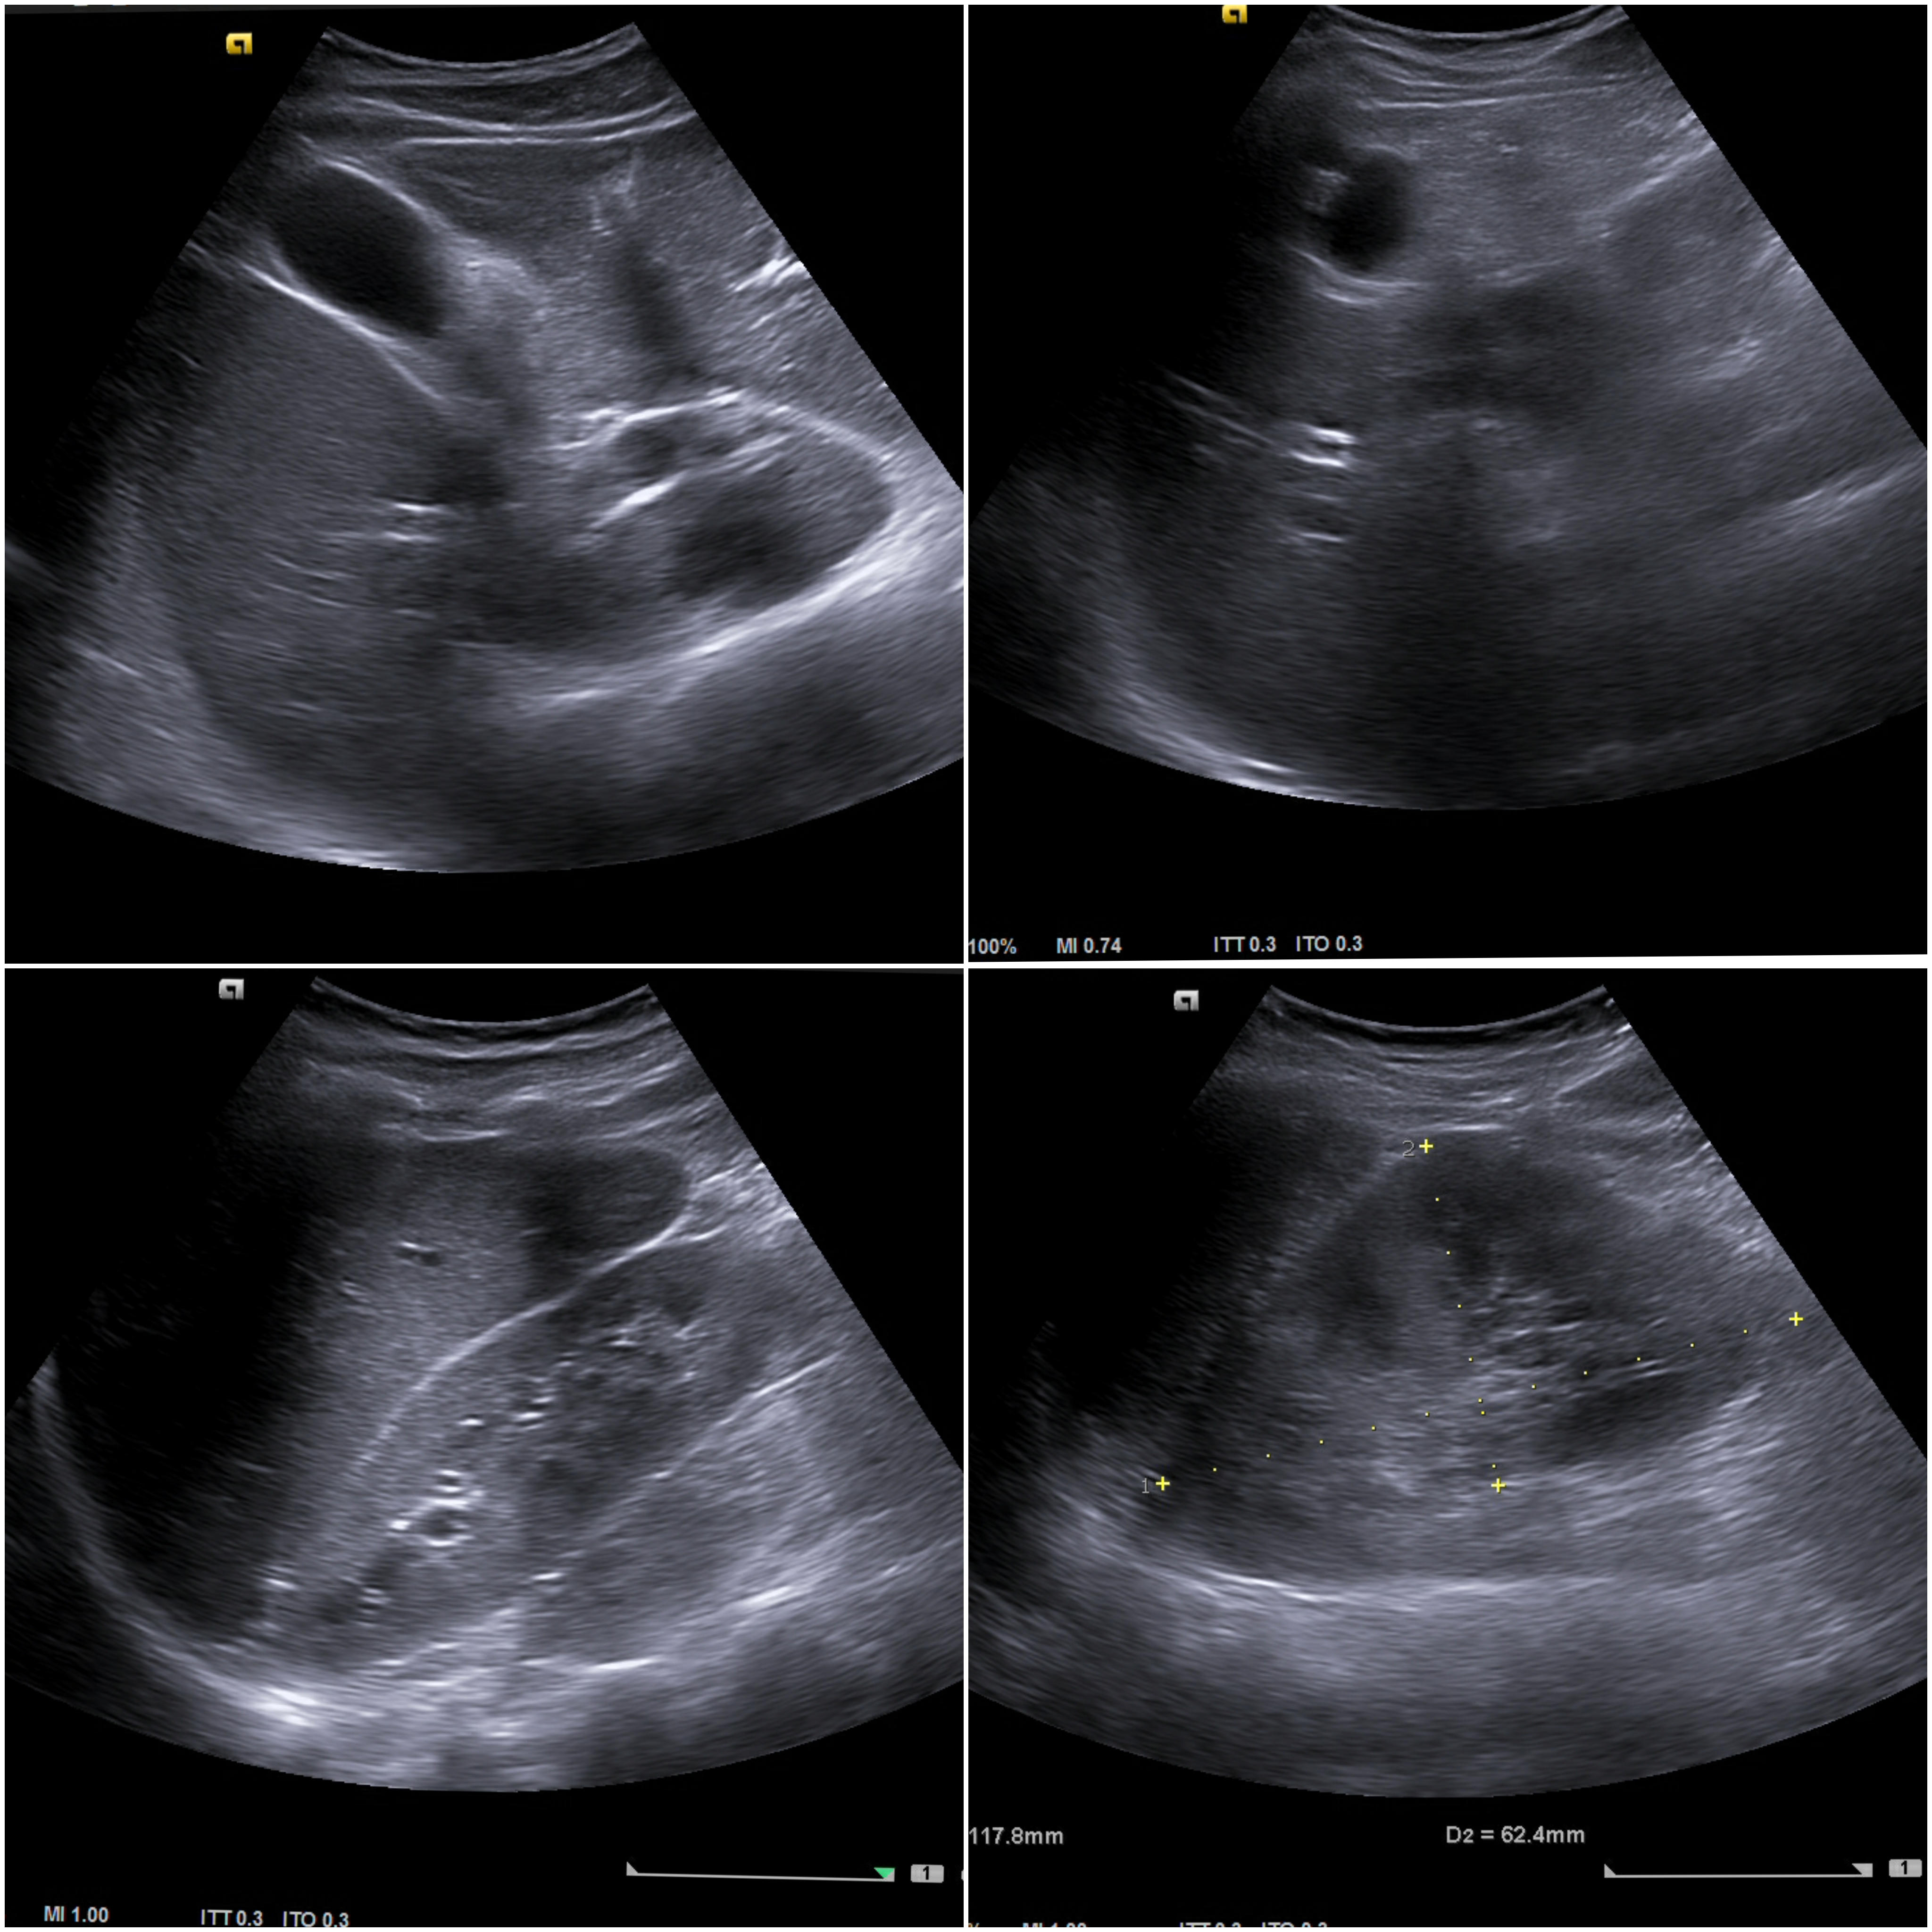

Ecografía clínica abdominal (ventana subóptima):

Parenquima hepatico sin alteraciones, vesícula biliar sin imagenes hiperecoénicas en interior. Pancreas visible en parte, sin alteraciones. Asimetría entre ambos riñones compatible variante de la normalidad RI. Llama la atención dilatación ilíaca derecha al comparar con contralateral y con aorta abdominal distal. Compatible con dilatación aneurismática ilíaca derecha.